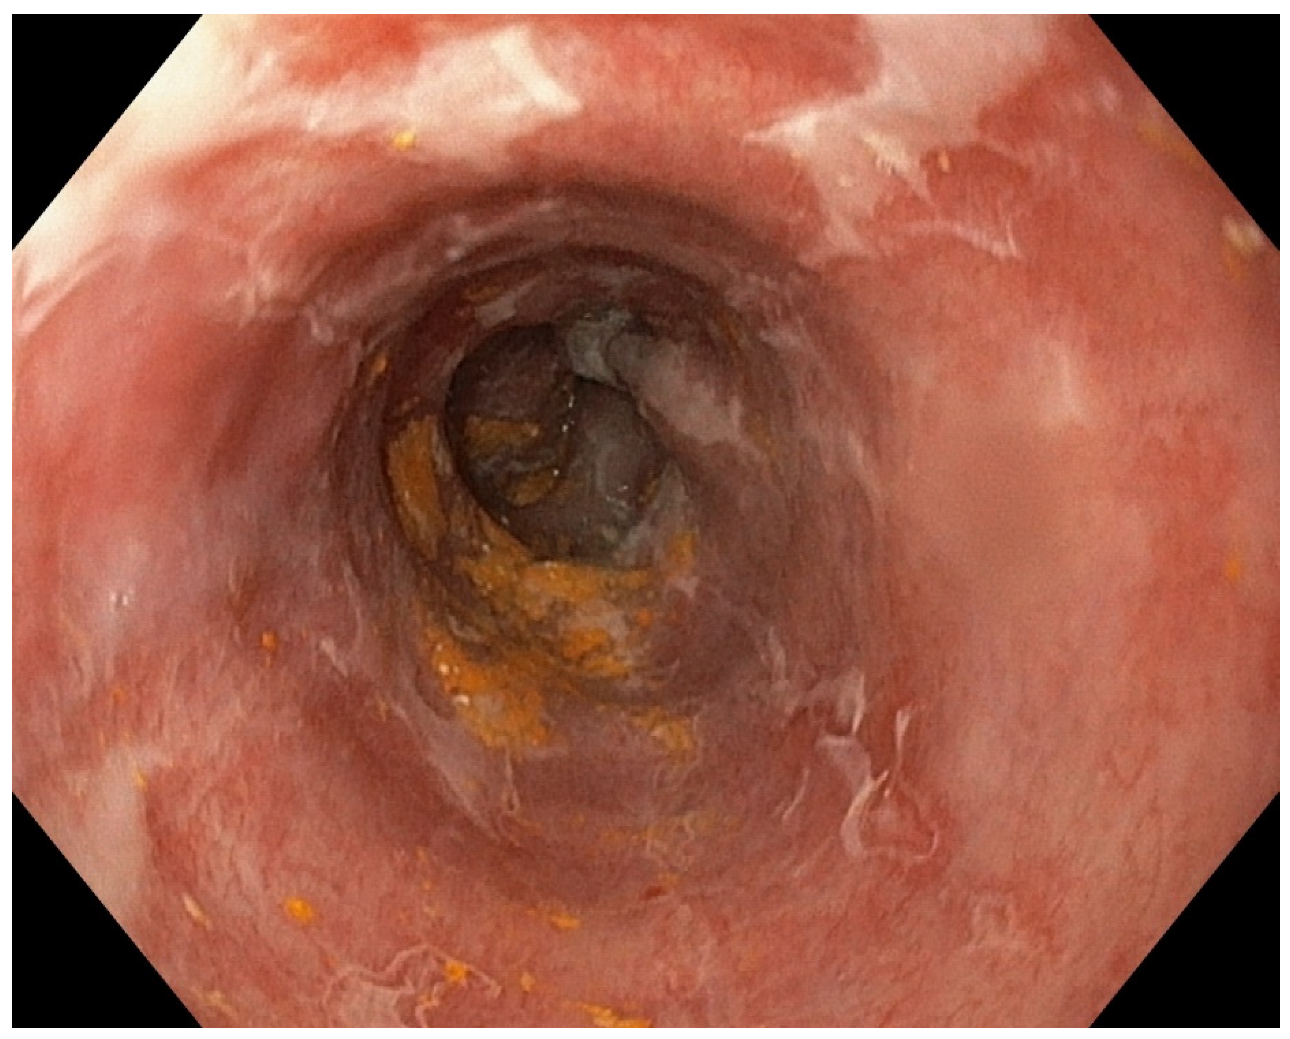

Acute Esophageal Necrosis in Acute Pancreatitis—Report of a Case and Endoscopic and Clinical Perspective

Grigore, M.; Enache, I.; Chirvase, M.; Popescu, A.L.; Ionita-Radu, F.; Jinga, M.; Bucurica, S. Acute Esophageal Necrosis in Acute Pancreatitis—Report of a Case and Endoscopic and Clinical Perspective. Diagnostics 2023, 13, 562. https://doi.org/10.3390/diagnostics13030562